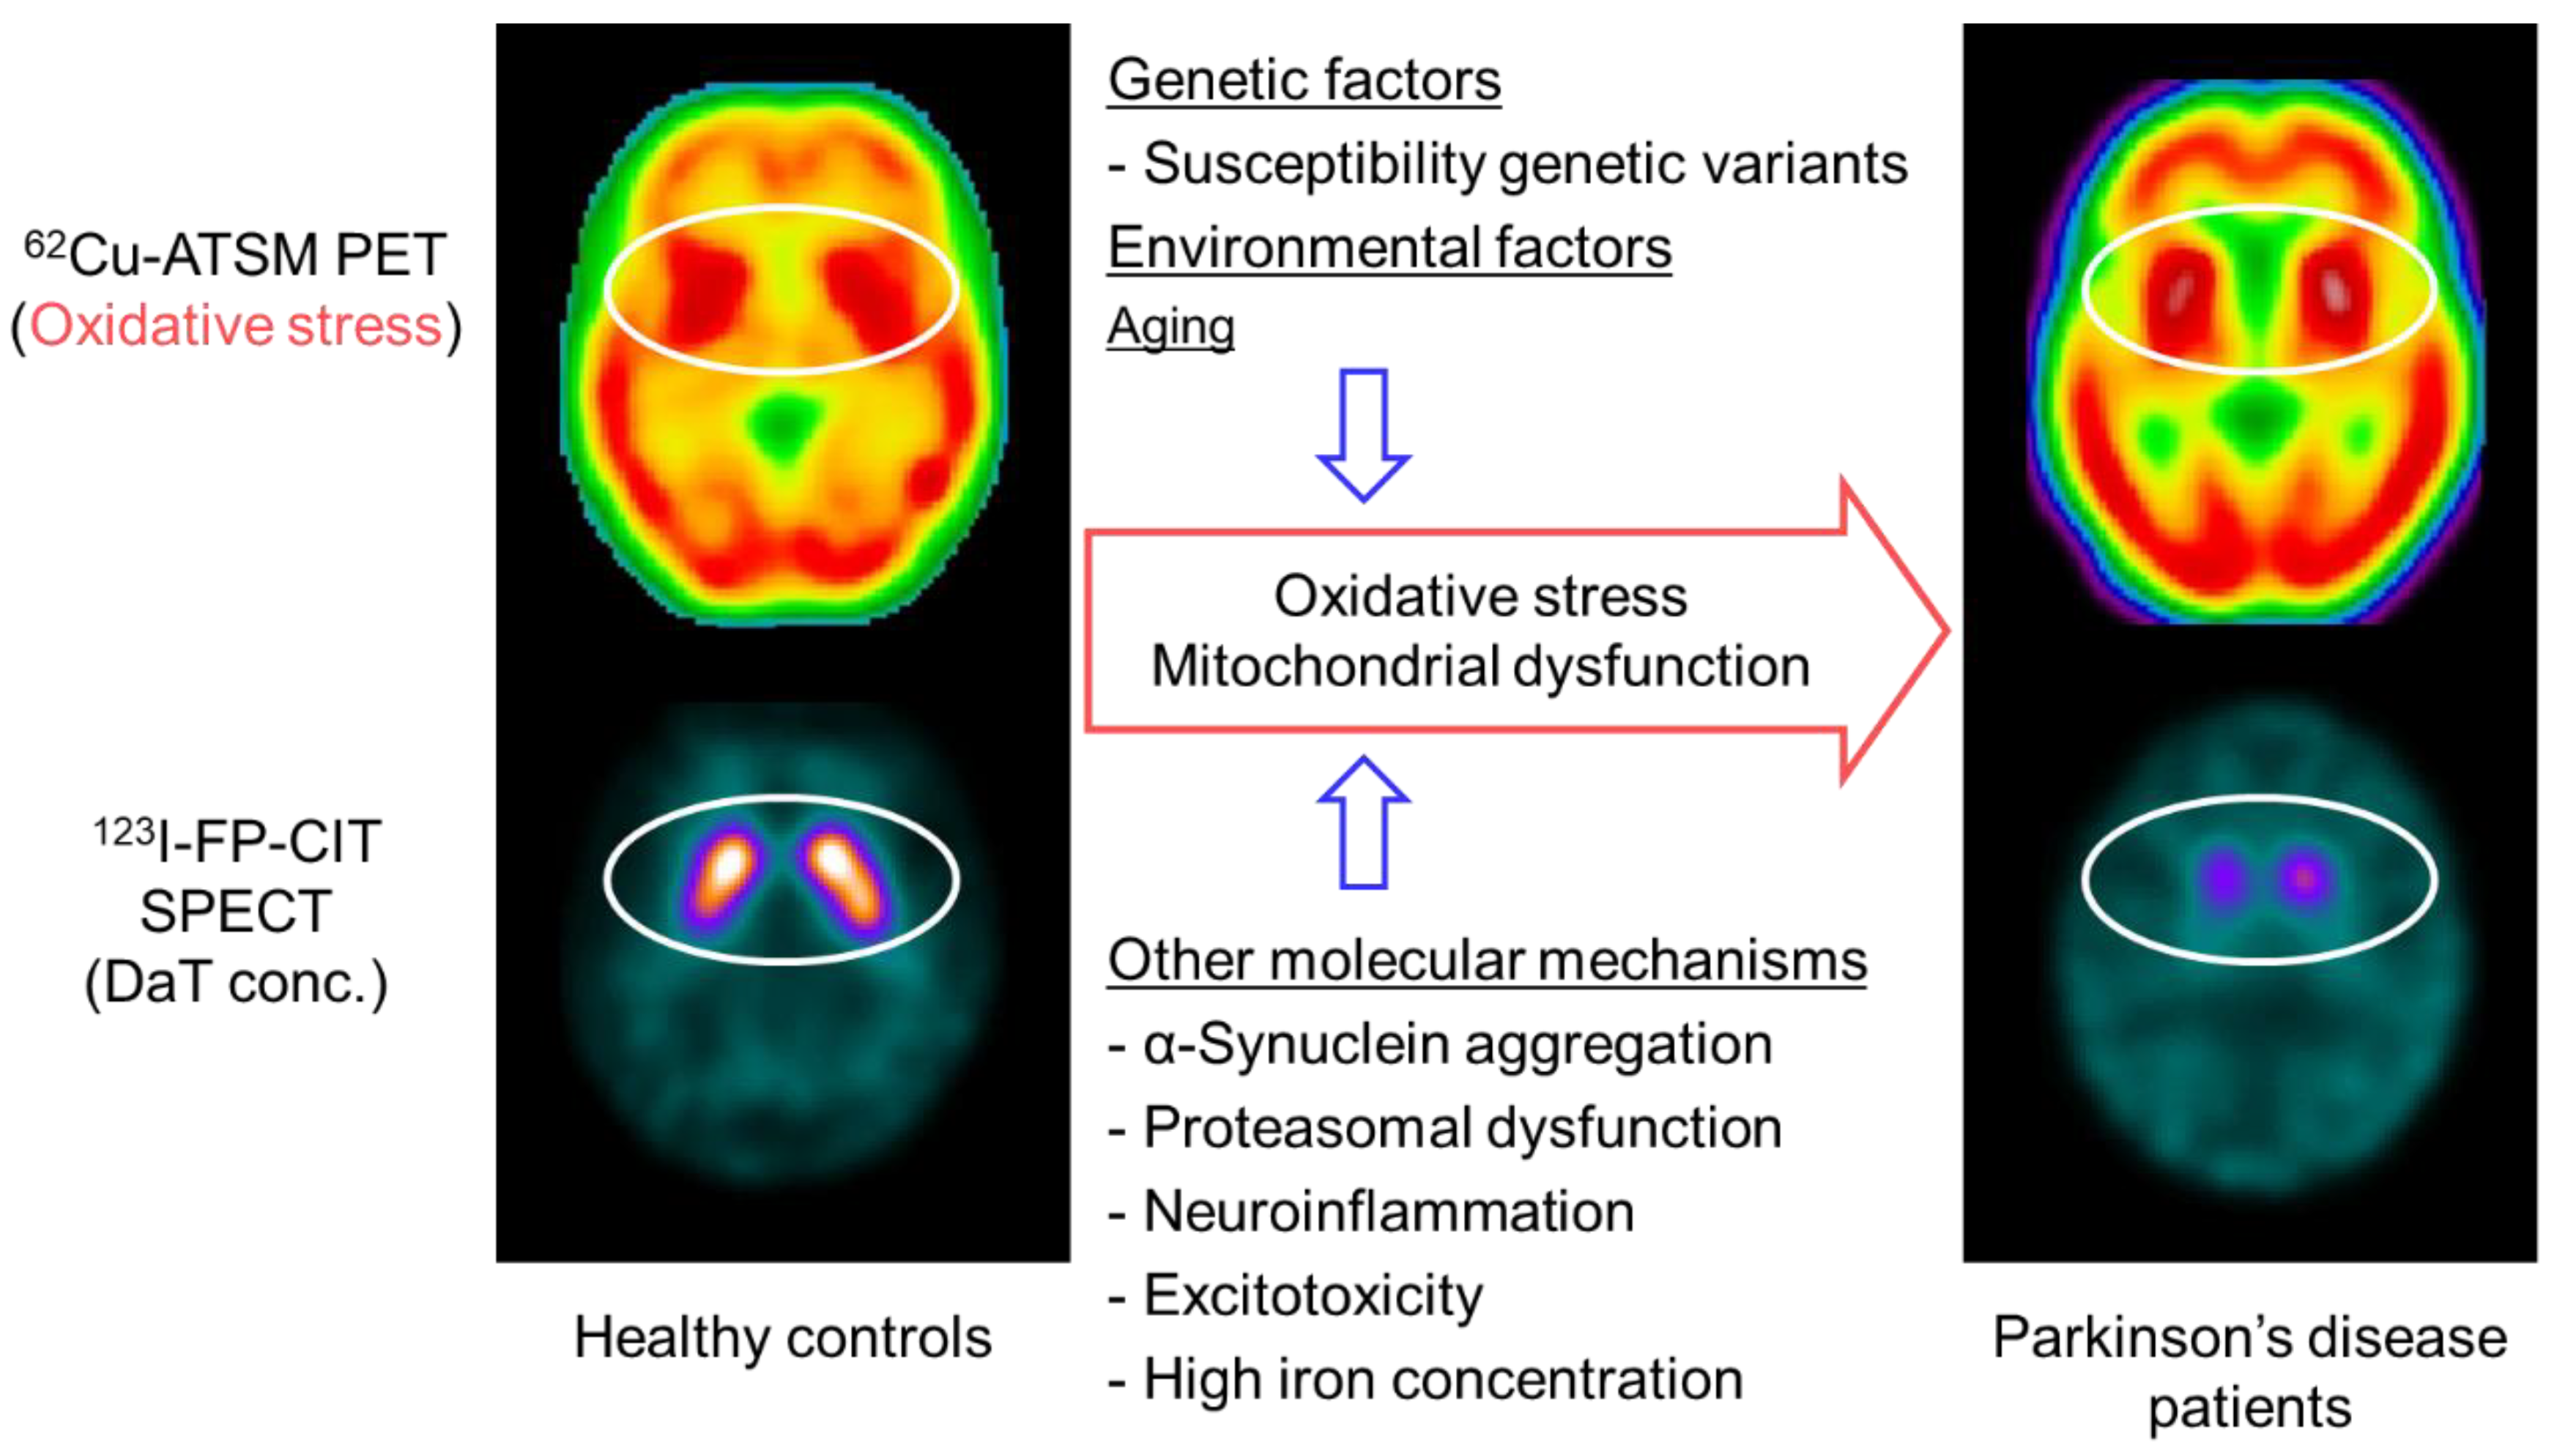

5.1. Oxidative Stress and Mitochondrial Dysfunction in Parkinson’s Disease

5.2. PET Imaging for Oxidative Stress in Patients with Parkinson’s Disease

5.3. PET Imaging for Neuroinflammation and Mitochondrial Activity in Parkinson’s Disease